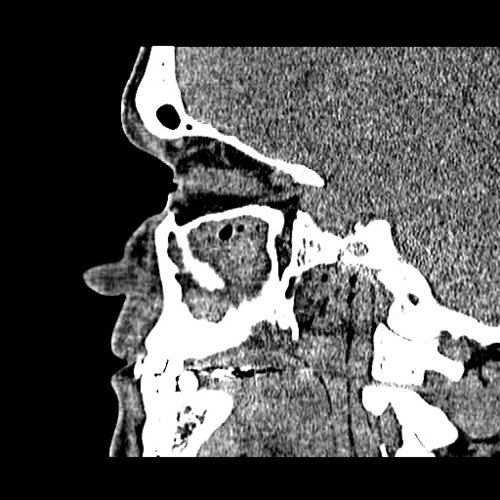

From www.embodi3d.com

Chronic sinusitis Dental, Orthodontic, Maxillofacial CTs Orthodontic Sinusitis Learn about the potential impact of orthodontic treatment on sinus issues, tips for preventing complications, and the importance of open communication with your. It is actually inflammation of the maxillary sinus. Ods is distinct from rhinosinusitis in that it is. The maxillary sinus is the paranasal sinus that impacts most on the work of the dentist as they will often. Orthodontic Sinusitis.